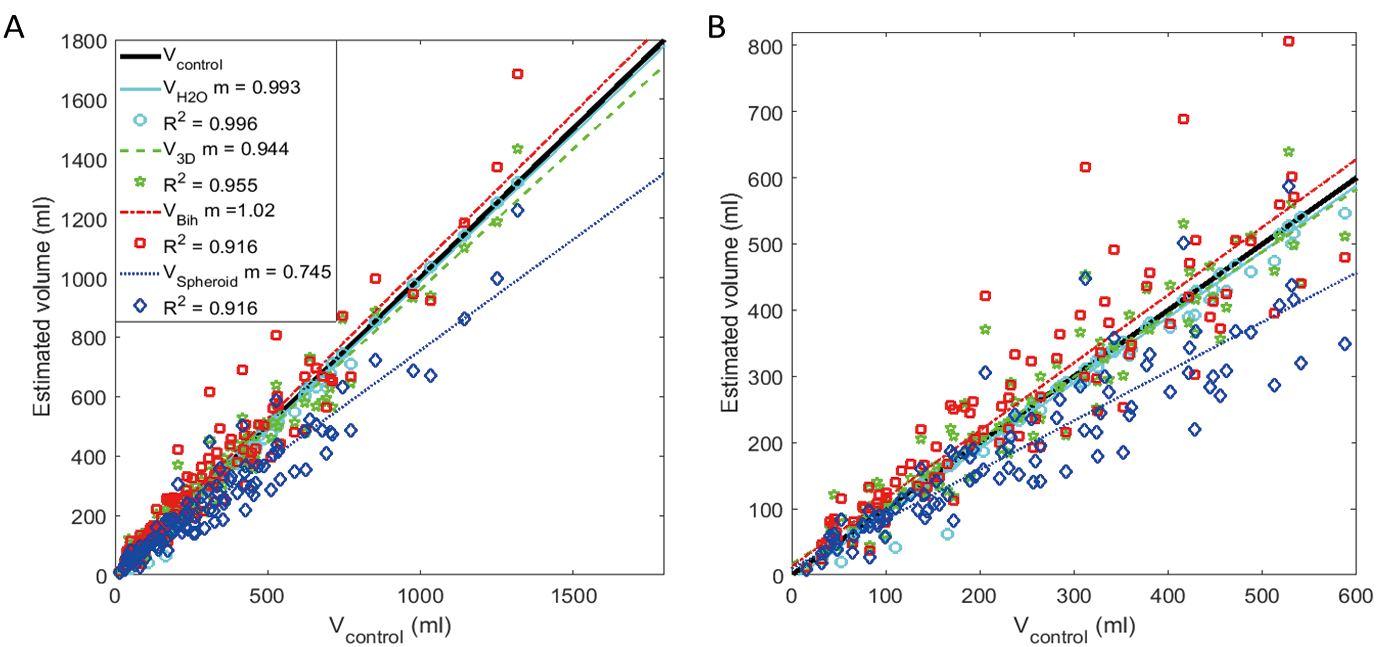

Methods: Twelve female participants with OAB completed an extended UD procedure with the addition of serial bladder ultrasound images captured once per minute. Bladder volume was measured using three ultrasound methods: (1) Vspheroid: two-dimensional (2D) method calculated assuming spheroid geometry; (2) Vbih: 2D correction method obtained by multiplying Vspheroid by a previously derived correction factor of 1.375; and (3) V3D: three-dimensional (3D) method obtained by manually tracing the bladder outline in six planes automatically reconstructed into a solid rendered volume. These volumes were compared to a control (Vcontrol) obtained by adding UD infused volume and the volume of estimated urine production.

Results: Based on linear regression analysis, both Vbih and V3D were fairly accurate estimators of Vcontrol, but V3D was more precise. Vspheroid significantly underestimated Vcontrol.

Conclusions: Although the Vbih and V3D methods were more accurate than the more-commonly used Vspheroid method for measuring bladder volumes during UD, the V3D method was the most precise and could best account for non-uniform bladder geometries. Therefore, the V3D method may represent the best tool required for the continued development of non-invasive methods to diagnose OAB and other forms of voiding dysfunction.